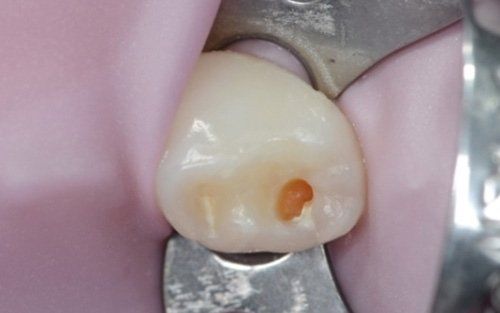

La carie nel bambino è una delle principali cause, insieme all’ortodonzia, di richiesta di intervento del dentista. La patologia ha una evoluzione particolarmente rapida in virtù della scarsità di smalto a difesa del dente da latte. Ciò comporta che, dal momento in cui il dente si ammala a quello in cui ne viene coinvolta la polpa (ovvero il nervo), il tempo sia veramente poco (vedi anche endodonzia pediatrica).